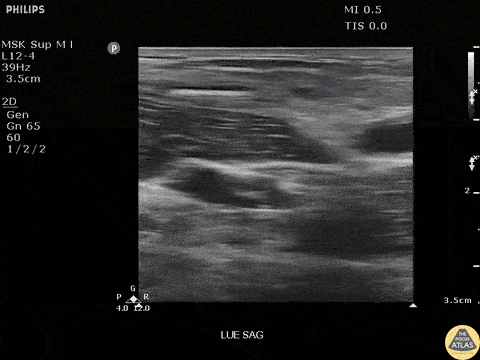

Soft Tissue - Bamboo Foreign Body

Seen here is a fragment of bamboo broken off in a patients arm. Patient had negative x-rays, emphasizing the importance of POCUS in identifying radiolucent foreign bodies. Image courtesy of Robert Jones DO, FACEP @RJonesSonoEM Director, Emergency Ultrasound; MetroHealth Medical Center; Professor, Case Western Reserve Medical School, Cleveland, OH View his original post here